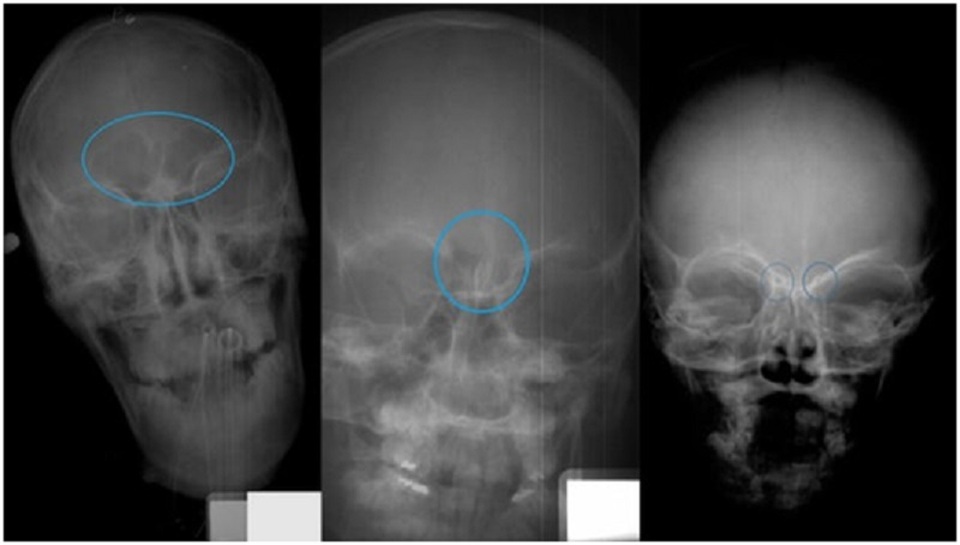

Trong quá trình thử nghiệm, các nhà khoa học đã tiến hành phân tích hình ảnh tia X của 392 trẻ em ở nhiều độ tuổi khác nhau - độ tuổi trong khoảng thời gian từ giữa tuổi thơ ấu cho đến khi trưởng thành (18 tuổi) - nhằm mục đích thiết lập các giai đoạn khác nhau trong quá trình phát triển ở trẻ.

Nhóm nghiên cứu cho biết hình ảnh của xoang trán không thể hiện trên hình ảnh chụp tia X do trẻ em ở lứa tuổi dưới 6 tuổi chưa hình thành xoang trán. Họ gọi giai đoạn này là Giai đoạn 0.

Giai đoạn tiếp theo là Giai đoạn 1, kéo dài trong độ tuổi từ 6 đến 8 tuổi (độ tuổi trung bình là 6,5 tuổi). Trong giai đoạn này, xoang trán bắt đầu hình thành hai hốc xương rỗng nhỏ ở vị trí đối xứng hai bên, phía sau trán.

Giai đoạn 2 là khoảng thời gian khi trẻ đạt từ 7 đến 10 tuổi (độ tuổi trung bình là 8 tuổi), khi đó, xoang vẫn chỉ là hai hốc nhỏ riêng biệt, tuy nhiên, bắt đầu từ giai đoạn này hai hốc xương có xu hướng phát triển tăng dần về kích thước và dần kết hợp lại với nhau.

Ở Giai đoạn 3 hay còn gọi là giai đoạn Cuối cùng - thời gian giữa độ tuổi 12 và 18 (tuổi trung bình là 16 tuổi), hai hốc rỗng sẽ phát triển kết hợp lại với nhau.